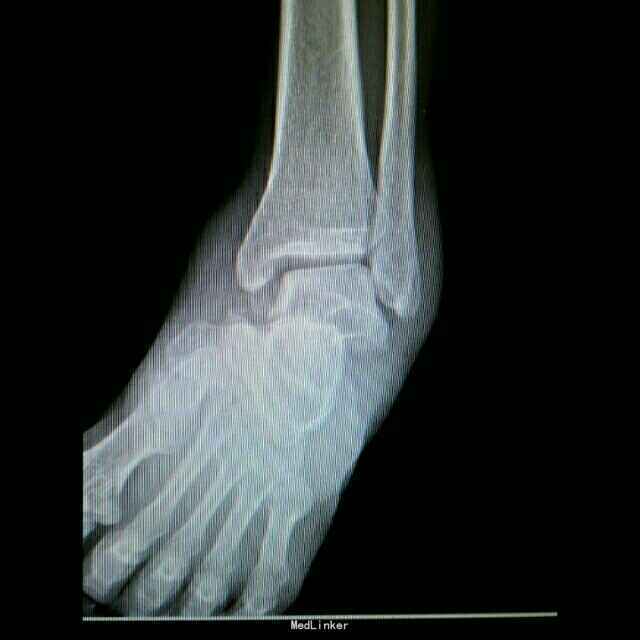

距骨骨折并脱位

骨折 距骨骨折

重物砸伤左足疼痛畸形14小时。

左踝至中足肿胀,左足内翻畸形,皮肤可见少许细小水泡,压痛,足背动脉搏动可,足趾活动可,感麻木。

距骨骨折并脱位 入院行闭合手法复位失败,予以跟骨牵引5天,石膏外固定3天,皮肤水泡、肿胀消退后行,距骨骨折脱位切开复位内固定+距舟关节融合。术后支具外固定,勿负重3个月。